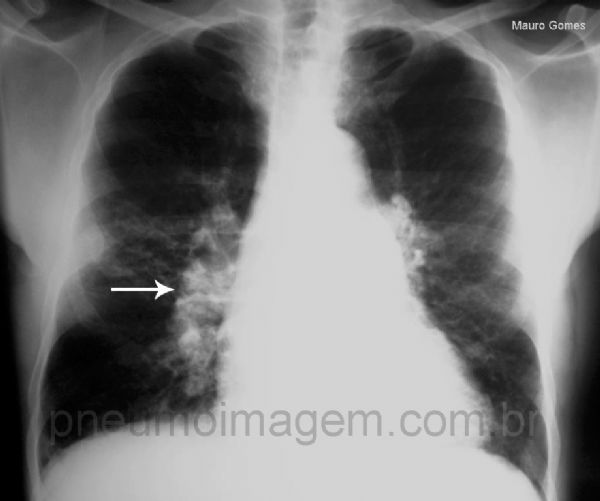

Na radiografia, os principais sinais são:

- Inversão do padrão vascular: vasos do ápice ficam mais calibrosos que os da base;

- Aparecimento das linhas de Kerley;

- Derrame pleural;

- Sinais de aumento do AE;

- Pode evoluir para Edema Agudo de Pulmão (EAP).